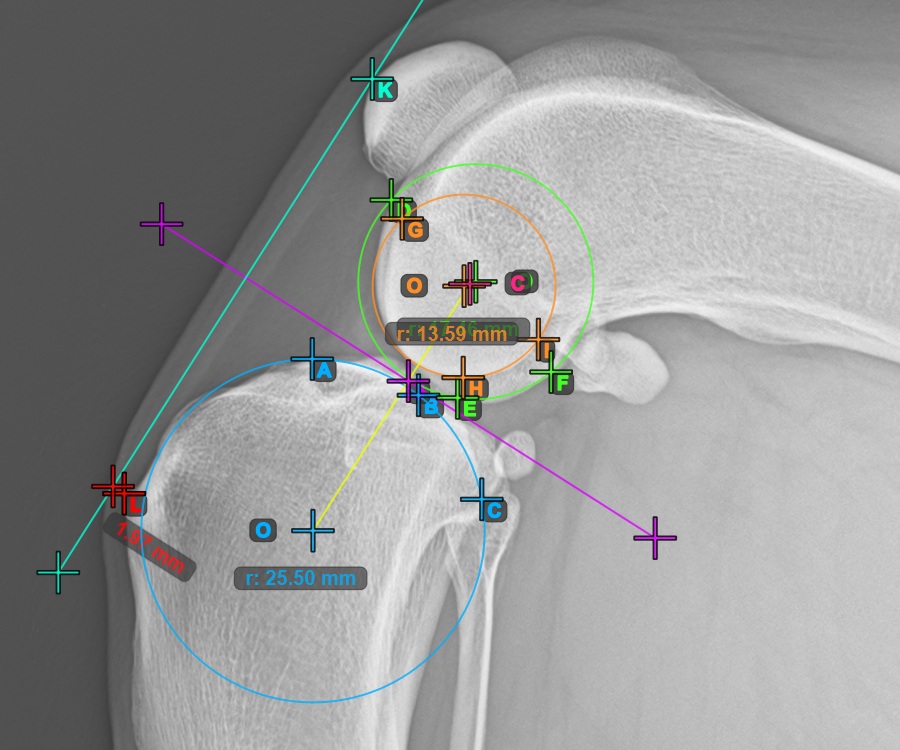

Mark the three points on the inner (secondary) condylus of the femoral bone (Condylus Femoris). Regardless of the order, make sure to mark the most cranial point, the most caudal point and the midpoint of the Condylus Femoris. A circle will be automatically constructed based on the three placed points.

The image below represents a typical placement of the three points on the second Condylus Femoris.